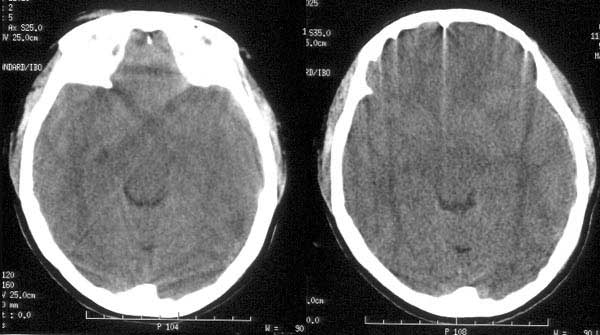

患者入院后予脱水治疗,并于10小时后行ct复查:

ct诊断:1、左颞硬膜下血肿已吸收消失。

2、蛛网膜下腔出血量较前增多。

3、脑肿胀程度较前明显改善。